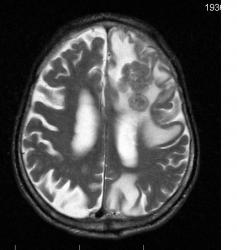

Мужчина 73 лет. За последний год похудел, потерял аппетит. Последний месяц стал плохо ходить, несколько раз падал, неделю назад стал психически не совсем адекватен. Врач - друг семьи, приехавший в гости, настоял на проведении МРТ головного мозга, рентгенографии ОГК и УЗИ брюшной полости. МРТ проводилось в медикаментозном сне, с реанимационным набором наизготовку, по немного укороченным программам. Все закончилось благополучно. Ничего сложного в плане диагностики. Просто не всегда бывает так много и ярко. Есть небольшое продолжение. Потом.

Т2 ВИ аксиальные сканы:

метастазы